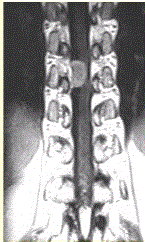

问题 患者女,52岁,颈部不适2年。MRI检查结果如下图。 病变的定性诊断为

选项 A.脊膜瘤 B.神经纤维瘤 C.神经鞘瘤 D.转移瘤 E.表皮样囊肿 F.血管瘤

答案 A

解析 A